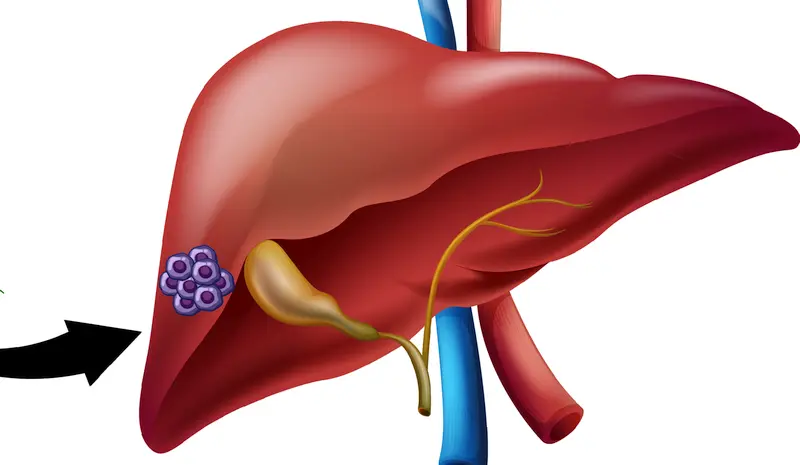

Uitgezaaid oogmelanoom betekent dat de kankercellen zich vanuit het oogmelanoom hebben verspreid naar andere delen van het lichaam, meestal naar de lever. Dit heet metastasering.

Het oogmelanoom ontstaat meestal in het vaatvlies (uvea) van het oog. De kankercellen kunnen zich verslepen en zich via het bloed verspreiden naar je organen. Bij oogmelanoom is de lever in ongeveer 90% van de gevallen de eerste plek waar uitzaaiingen ontstaan.

- Leverchirurgie

Wanneer er uitzaaiingen in slechts een deel van de lever zitten, kan de chirurg dat deel van de lever verwijderen. Dat kan alleen als na operatie er voldoende gezond leverweefsel overblijft en de patiënt een dergelijke operatie aankan. Vaak komt de kanker daarna toch weer terug, omdat er al elders nog niet zichtbare uitzaaiingen aanwezig waren. - Radio Frequency Ablation (RFA)

In het LUMC worden leverperfusies uitgevoerd bij oogmelanoom patiënten met uitzaaiingen in de lever. Hierbij wordt chemotherapie lokaal in de lever gebracht via een katheter in de leverslagader. De behandeling zit niet in het zorgpakket, maar wordt betaald door het ziekenhuis (LUMC). - Immuuntherapie

Radio-embolisatie is een vorm van inwendige bestraling in de lever om uitzaaiingen in de lever te behandelen.

Via de leverslagader worden radioactieve bolletjes naar de tumor gespoten. Die bolletjes lopen vast in de bloedbanen rondom en in de tumor. Daar vindt de inwendige bestraling plaats: de bolletjes geven hun radioactiviteit af om de tumorcellen te vernietigen.

Hoe gaat radio-embolisatie in zijn werk?

De interventieradioloog brengt via je liesslagader een katheter in uw leverslagader om heel kleine radioactieve bolletjes toe te dienen. Die bolletjes lopen vast in de bloedvaten rondom de tumor en geven daar hun radioactiviteit af. Voordat je de behandeling ondergaat, vindt er eerst een uitgebreid onderzoek plaats, waarbij alle bloedvaten die niet naar de lever gaan, worden afgesloten. Met behulp van een radioactief stofje wordt gecontroleerd of er inderdaad alleen opname is in de lever.

Vervolgens wordt een week later de radio-embolisatie uitgevoerd. Voordat je deze behandeling krijgt, is er overleg tussen de specialisten binnen het behandelend team: daarbij zijn dan aanwezig een interventieradioloog, de chirurg, de maag- darm- en leverarts, een nucleair geneeskundige en de oncoloog.